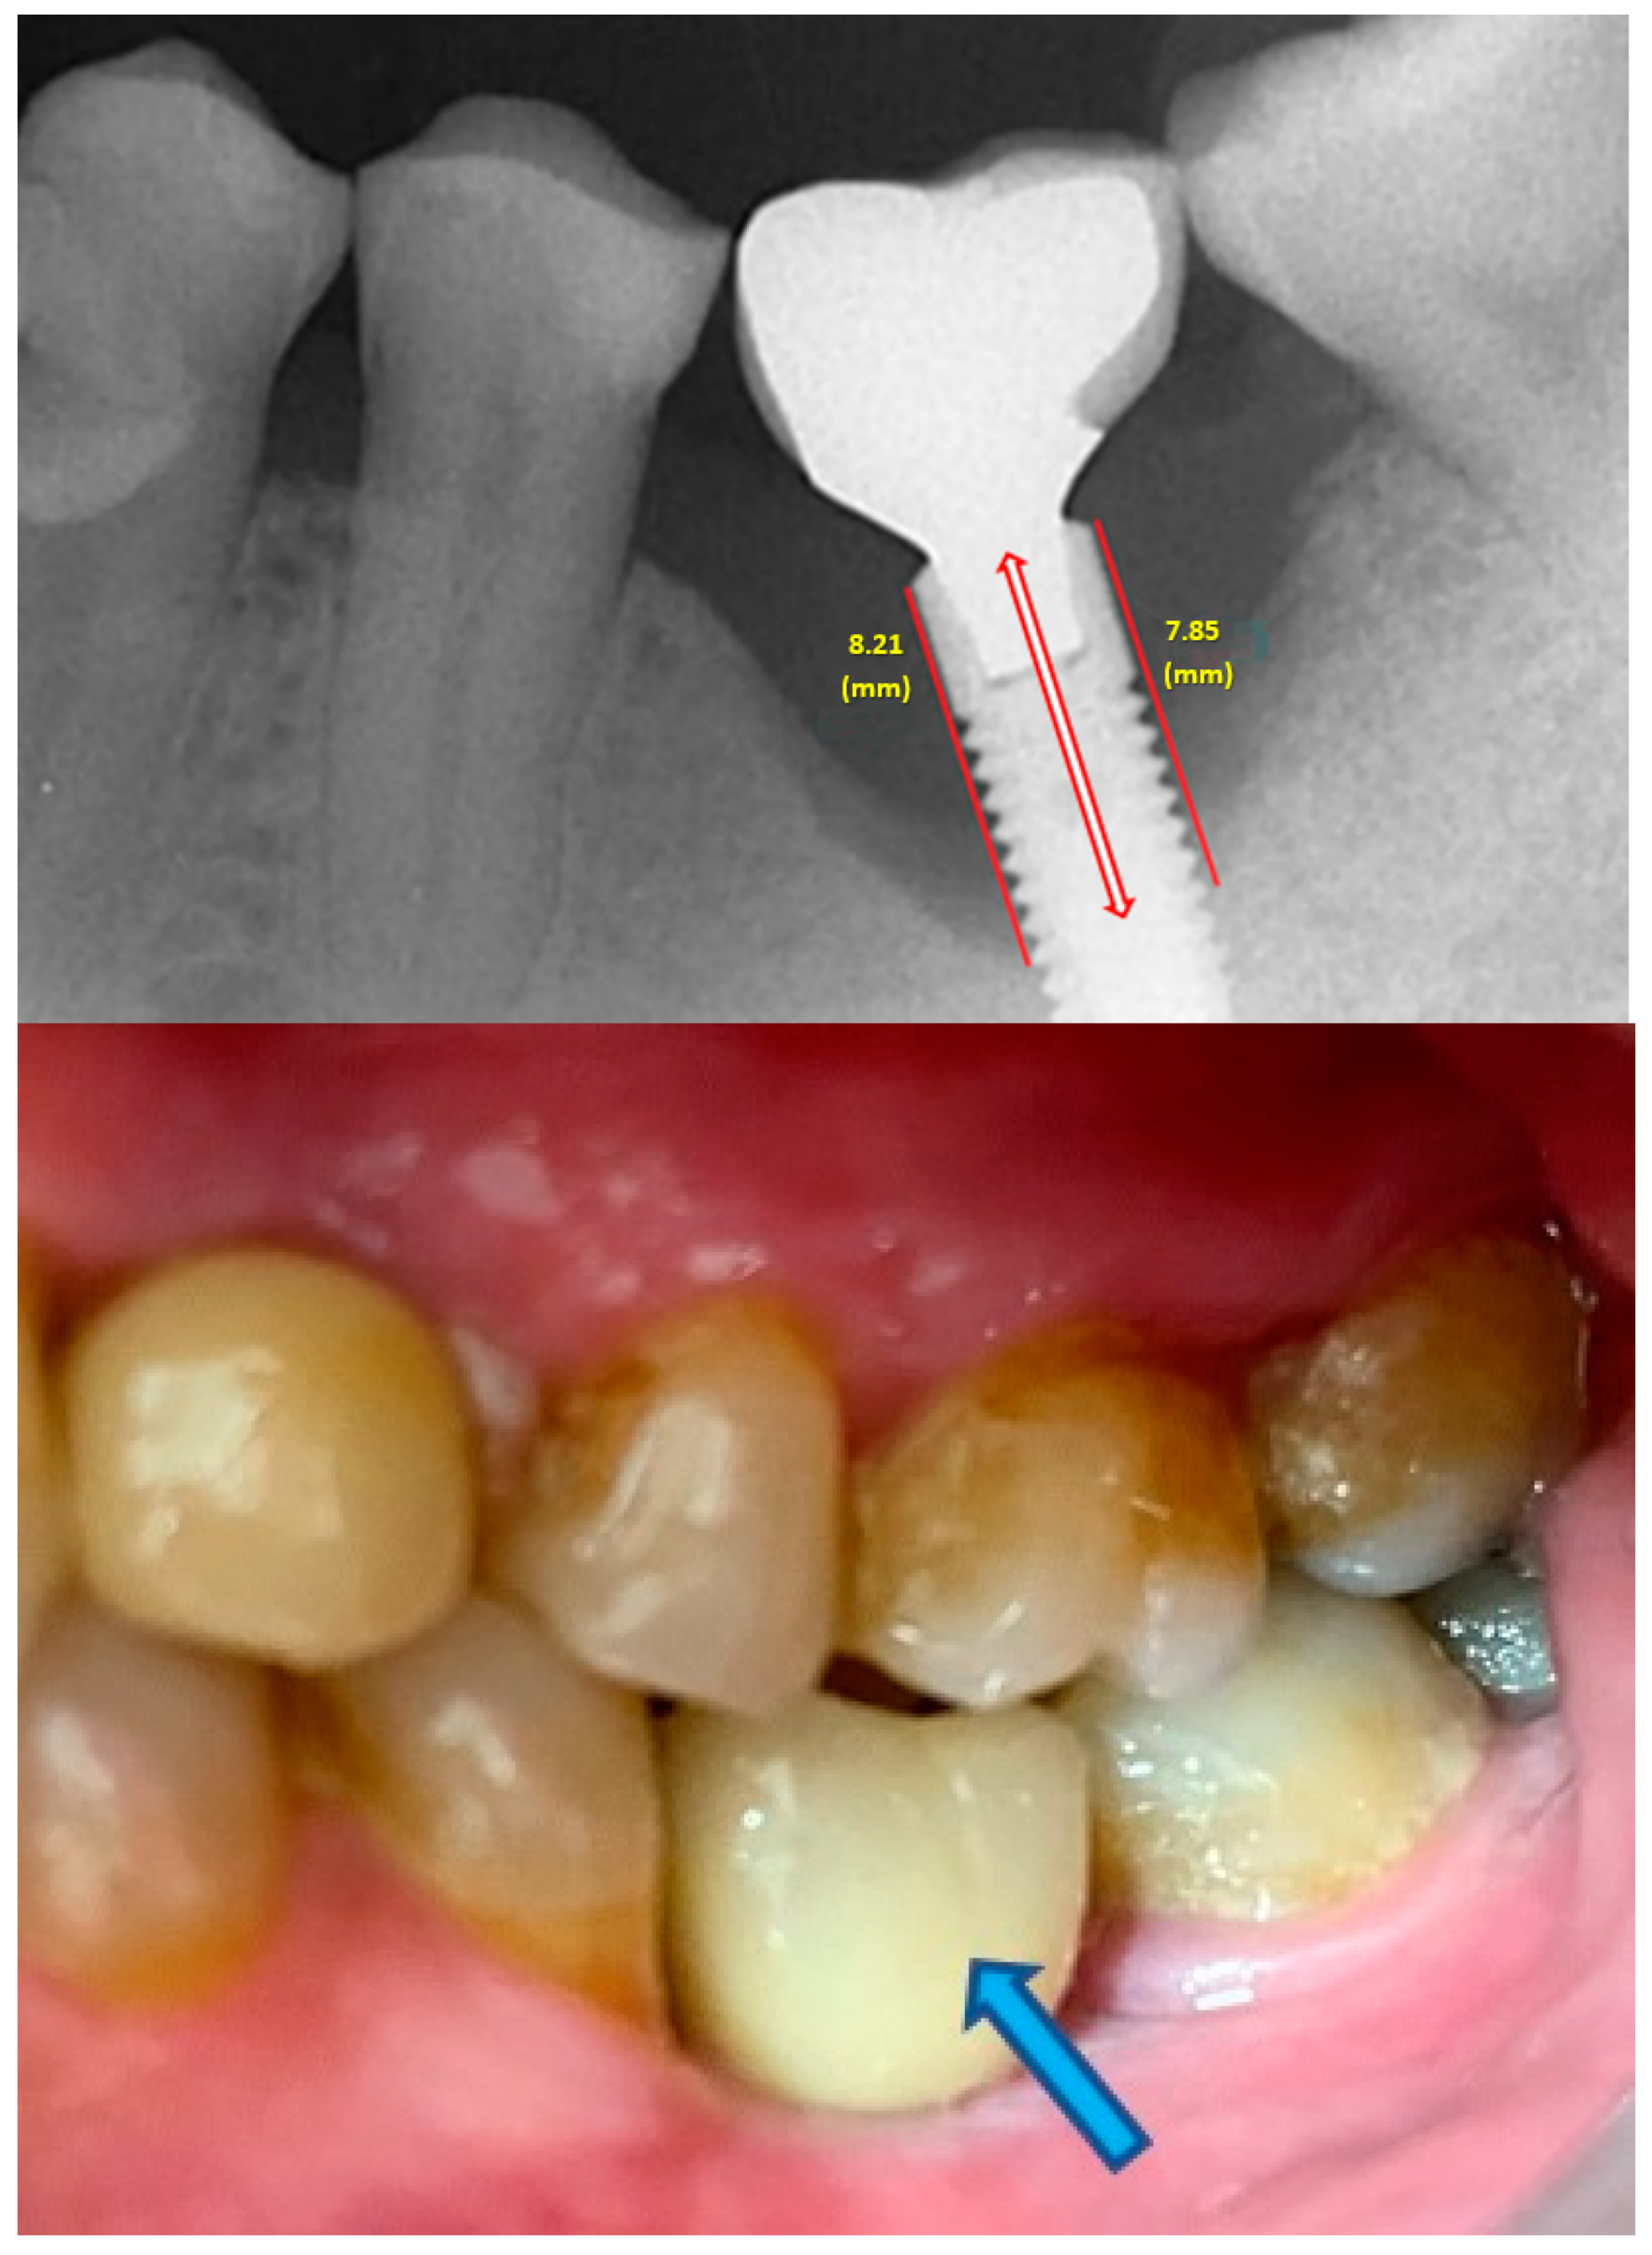

- Measurement of mesial and distal bone loss: Clinically, an increase in the probing depth of the peri-implant pockets, both mesial and distal, was recorded using a calibrated probe with a force of 0.25 N. Radiographically, mesial and distal peri-implant bone height loss was measured using properly performed radiological projections. In fewer than five patients, statistically significant findings in cases of bone loss were difficult to achieve.

- Measurement of the mesial and distal cantilever: The mesial cantilever was significantly greater for the bilateral bone loss group (1833.5 ± 1531.4 µm) compared to the group without MBL (1029.5 ± 968.6 µm) (F = 2.77; p < 0.05). Concerning the effect of the mesial versus distal cantilever, although the mesial cantilever appears to be more favorable, the only article found in the literature regarding this finding is a study by Romeo et al. (2003), which showed that this effect is not always consistent, although the difference is minimal [31].

| Implant diameter (mm) | 3.80 | 0.5 | 3.90 | 0.5 | 3.8 | 0.4 | F = 0.16; p = 0.85 |

| Implant length (mm) | 10.0 | 1.2 | 10.7 | 1.4 | 10.6 | 1.7 | F = 1.33; p = 0.268 |